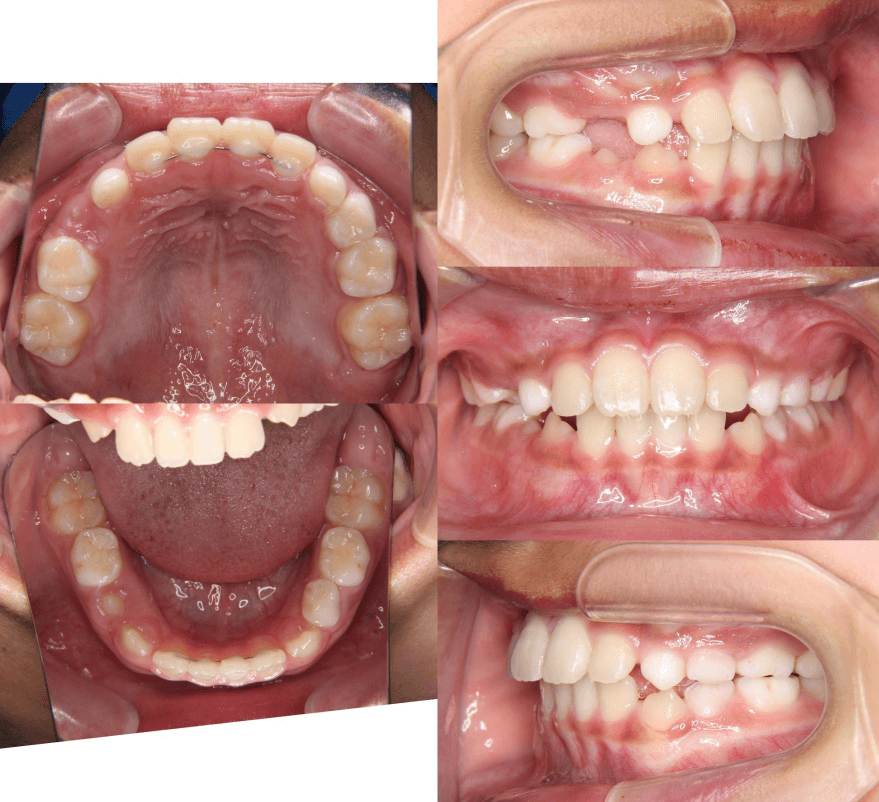

早期矯正治療 反対咬合症例②

主訴 | 前歯の噛み合わせが逆で、見た目や食事に違和感があることを心配されて来院されました。 |

---|---|

診断結果 | 7歳8か月の男児 前歯の反対咬合診断 |

治療内容 |

|

治療後の経過 | 早期矯正治療は11歳5か月で終了し、現在は3〜4か月ごとの定期検診で経過観察中で、今後本格的な矯正治療へ移行予定です。 |

治療期間 | 3年6か月 |

治療費用 | 430,000円(税別) |